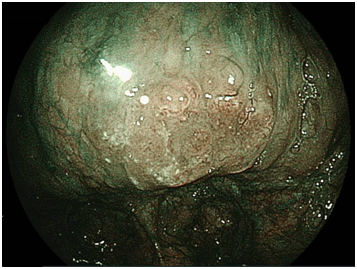

We detected 11 cases of superficial squamous cell carcinoma of the base of the tongue between April 2012 and March 2016. All the patients were complicated with current (n=3) or previous (n=8) esophageal squamous cell carcinoma. The patient characteristics are shown in Table 1. The mean age of the patients was 63.7years (range, 49-73years), and all patients were male. Four cases were diagnosed using trans-nasal endoscopy with the FICE system, seven cases were diagnosed using trans-nasal endoscopy with the LASERIO system. The average time to complete a thorough examination for one patient was approximately from 1 to 2minutes, regardless of the presence of abnormal findings. Biopsy specimen were obtained in all patients, and diagnosed as squamous cell carcinoma pathologically. Table 2 shows the treatment results. Five lesions were flat type (Figure 4A), four were elevated (Figure 4B), and two were depressed (Figure 4C). Regarding the tumor size, eight were T1, three were T2. No lymph node metastasis was detected in any case. Six cases were treated by endoscopic laryngo-pharygeal surgery,15 and 3 cases were treated by chemo-radiotherapy. One case was followed because of esophageal cancer. One case was treated by trans-oral robotic surgery at another hospital. For the seven resected specimens, the median tumor thickness was 800μm (range, 250-3000μm), and the median tumor diameter was 11mm (range, 10-25mm). Histologically, two of these lesions were squamous cell carcinoma in situ, five showed microinvasion of the subepithelial tissue. During a median follow-up period of 26months (range,11-56months), 1 patient, which patient’s tumor thickness was 3000μm, developed lymph node metastasis, which was treated by neck lymphadenectomy and chemo-radiotherapy. Three of the 11 patients cases were died of another disease, and 8 were alive as drafting this manuscript.

Figure 4C Depressed type.